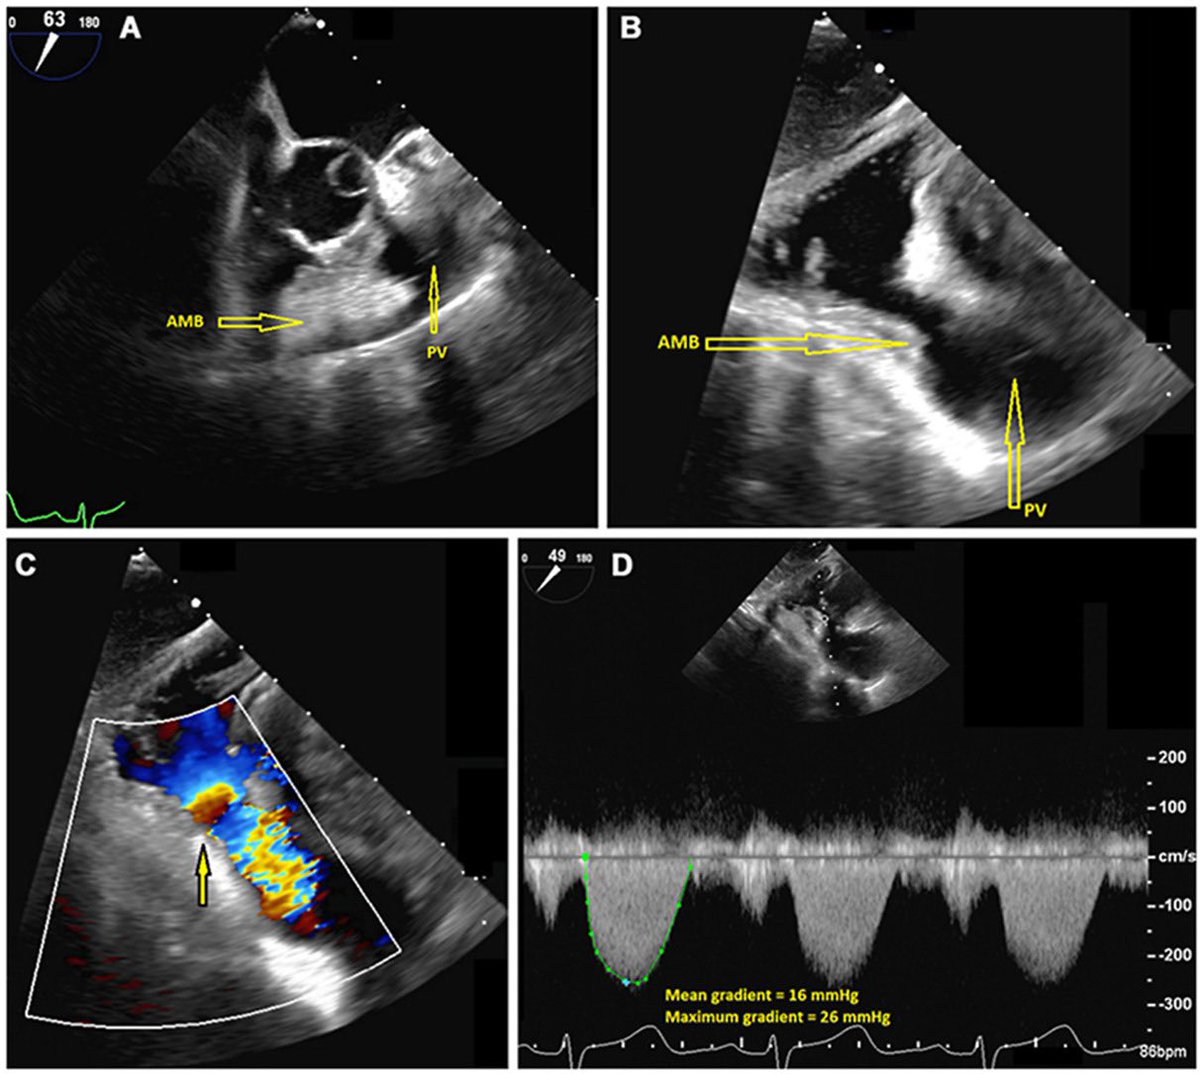

This @ISACHD #CaseOfTheMonth is a 67-year-old with a history of ascending aortic #aneurysm, mixed aortic valve disease, presenting with a syncopal event. She was found to have a #double-chambered #right #ventricle with no known history of a ventricular septal defect.